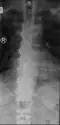

| DISH in an 80 year old female, also with T11 fracture. | |